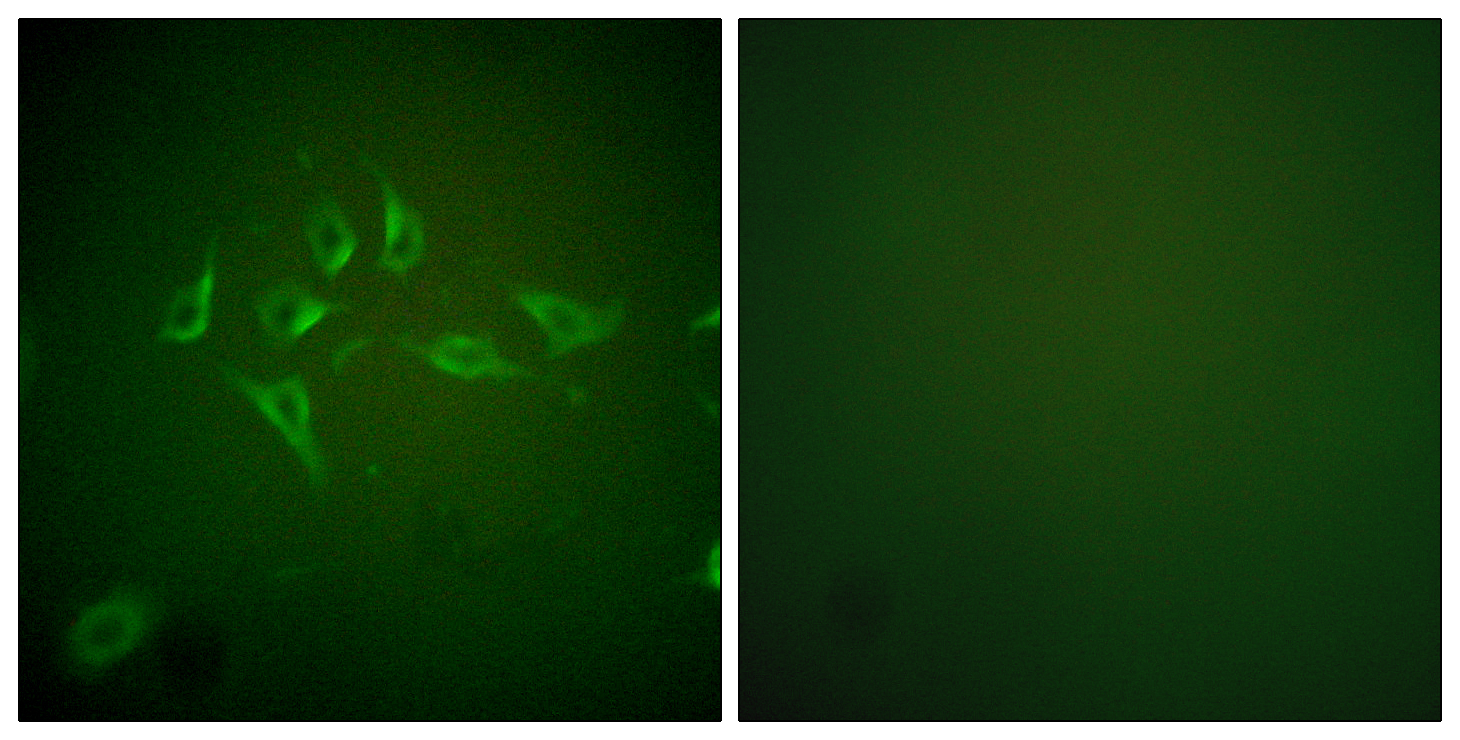

ApplicationsImmunoFluorescence, Western Blot, ELISA, ImmunoHistoChemistry

- ApplicationsImmunoFluorescence, Western Blot, ELISA, ImmunoHistoChemistry

- Scientific DescriptionRabbit polyclonal antibody to iNOS.

- ReactivityHuman

![iNOS antibody [N1N2-2], N-term detects iNOS protein at cytoplasm in human colon cancer by immunohistochemical analysis. Sample: Paraffin-embedded human colon cancer. iNOS antibody [N1N2-2], N-term (GTX124210) diluted at 1:400.

Antigen Retrieval: Citrate buffer, pH 6.0, 15 min](https://www.genetex.com/upload/website/prouct_img/normal/GTX124210/GTX124210_40751_20160523_IHC-P_w_23060522_255.webp)